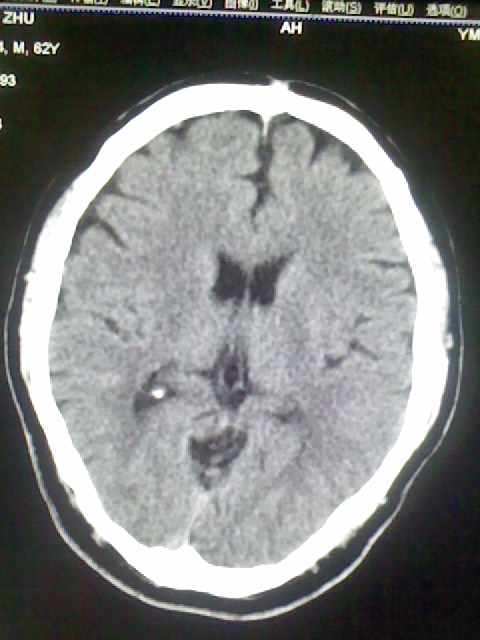

标题: CT15555:头痛 10余日 来诊大家帮忙看看 [打印本页]

标题: CT15555:头痛 10余日 来诊大家帮忙看看

脑萎缩

脑沟、裂增宽,提法脑萎缩,建议mt检查。

脑萎缩,以小脑为著。

脑沟、裂增宽,提示脑萎缩

老年脑

支持轻度脑萎缩。